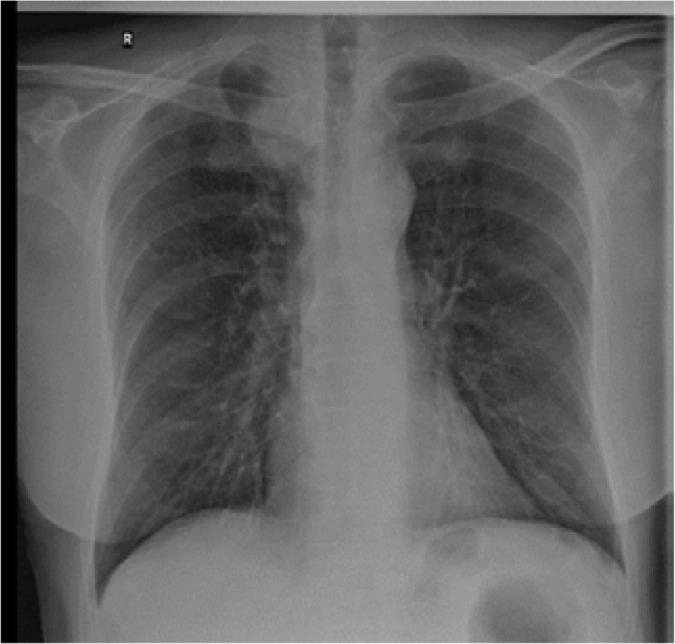

Arthritis is an unusual manifestation of paraneoplastic syndrome, appearing in a variety of cancers, including pulmonary and colorectal. It can often pose a diagnostic challenge to physicians, since it may be difficult to distinguish from more commonly encountered rheumatic illnesses. Moreover, synchronous cancers are rare and unexpected in patients with symmetrical polyarthritis. Hypertrophic pulmonary osteoarthropathy is to be considered in patients with polyarthritis and lung neoplasia. The aim of this report is to highlight the case of a patient presenting with paraneoplastic polyarthritis, which led to identifying the presence of underlying synchronous lung and colorectal malignancies. Lymph node biopsy was performed raising suspicion of Caplan's syndrome but lung lobectomy confirmed adenocarcinoma. Rheumatologists should be reacquainted with rheumatic manifestations in malignant diseases.

关节炎是副肿瘤综合征的一种不寻常表现,出现在多种癌症中,包括肺癌和结直肠癌。它常常给医生带来诊断挑战,因为可能难以与更常见的风湿性疾病相区分。此外,在对称性多关节炎患者中,同时发生的癌症罕见且出乎意料。对于多关节炎和肺肿瘤患者,应考虑肥厚性肺骨关节病。本报告的目的是强调一例出现副肿瘤性多关节炎的患者病例,该病例导致发现了潜在的同时存在的肺癌和结直肠癌。进行了淋巴结活检,引发了对卡普兰综合征的怀疑,但肺叶切除术确诊为腺癌。风湿病学家应重新熟悉恶性疾病中的风湿性表现。